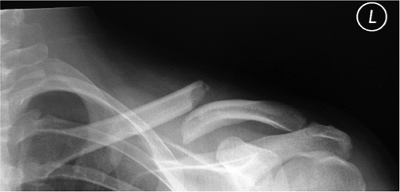

confirmed with a radiograph of the injured shoulder. Usually, a

standard anteroposterior (AP) view of the clavicle is enough to

establish the definitive diagnosis (Fig. 1.2).

Figure 1.2. Preoperative AP radiograph demonstrating a midclavicular fracture with shortening and overriding of the fracture.